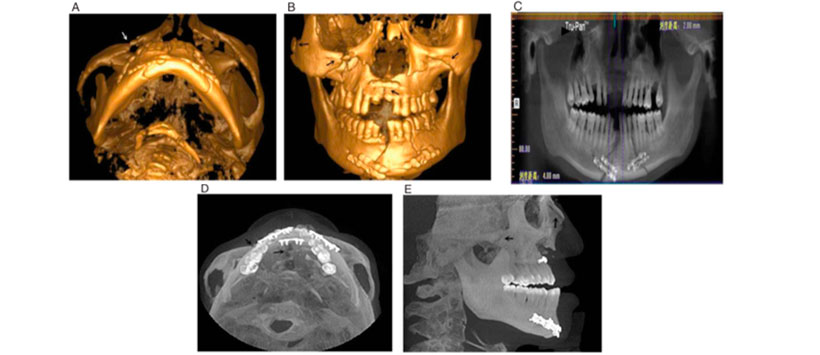

La CBCT también puede generar imágenes estáticas en 3D e imágenes reconstruidas giratorias. Además, las imágenes estáticas en 3D pueden proporcionar información en 3D sobre un sitio específico, mientras que las imágenes giratorias en 3D se pueden rotar en cada dirección, y se pueden observar cambios en los dientes y el hueso alveolar antes, durante (Figura 1) y después del tratamiento (Figura 2). Una comparación de las ventajas y desventajas de las modalidades radiológicas comunes utilizadas para evaluar las fracturas maxilofaciales se presenta en la Tabla 1.